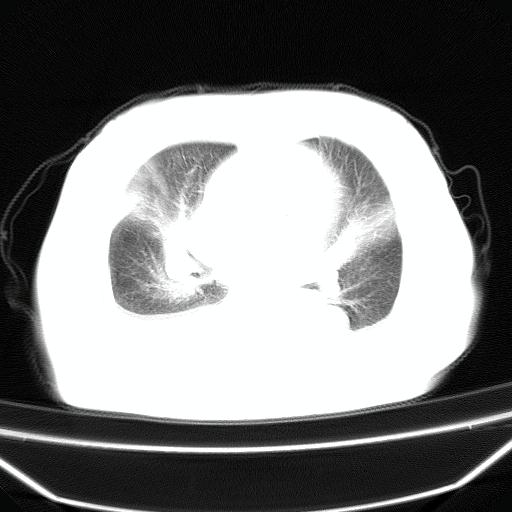

以下是引用jiangjing在2008-4-20 10:43:00的发言:[br]结合病史支持 冠心病[冠状动脉钙化],心功能不全,肺淤血、肺水肿,双侧胸腔与斜裂积液

以下是引用liuyue在2008-4-19 22:25:00的发言:[br]先考虑:1.心衰伴肺水肿、双侧胸腔积液、叶间积液、双下肺不完全性肺不张; [br] 2.冠状动脉粥样硬化。